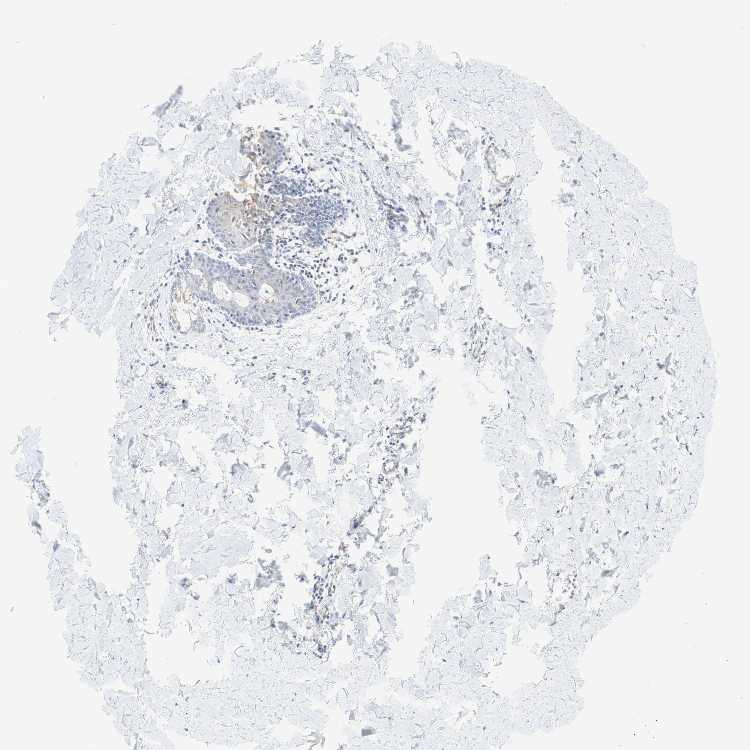

SKIN 2 - Antibody stainingi

Antibody staining in the annotated cell types in the current human tissue is reported as not detected, low, medium, or high, based on conventional immunohistochemistry profiling in selected tissues. This score is based on the combination of the staining intensity and fraction of stained cells.

Each image is clickable and will lead to virtual microscopy that enables deeper exploration of all samples and also displays staining intensity scores, fraction scores and subcellular localization as well as patient and tissue information for each sample.

Antibody HPA001813Antibody CAB009228

Cells in basal layer -Medium

Cells in corneal layer -Not detected

Cells in granular layer -Low

Cells in spinous layer -Low

Endothelial cells -Low

Epidermal cells Medium-

Extracellular matrix -Low

Fibrohistiocytic cells -Not detected

Langerhans cells -Not detected

Lymphocytes -Not detected

Melanocytes -Not detected

Vascular mural cells -Not detected